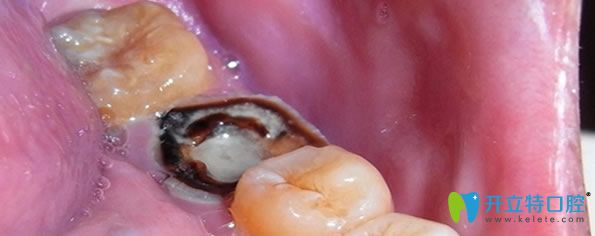

一、急性牙髓炎如何治療?

急性牙髓炎主要是細(xì)菌感染引起牙髓組織的急性炎癥,遇冷更加疼痛。急性牙髓炎發(fā)病急,疼痛劇烈,牙齦紅腫、化膿等癥狀,一般鎮(zhèn)痛藥物效果不明顯,遇到良心牙醫(yī)會(huì)保存活髓及患牙,利用開髓及藥物來緩解疼痛,服用消炎藥兩到三天,疼痛緩解后,嚴(yán)重的牙髓炎可采取根管治療或者活髓切斷術(shù),能夠及時(shí)預(yù)防病情嚴(yán)重及擴(kuò)散。沒有保存價(jià)值的牙齒可拔掉。

急性牙髓炎治療方法